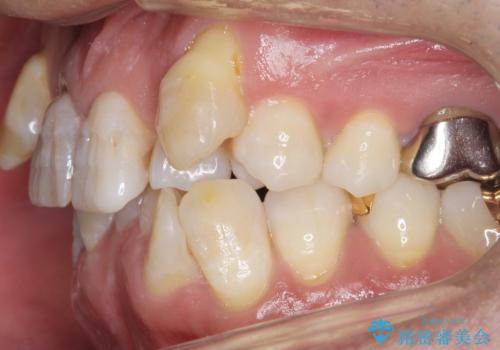

奥に引っ込んでいる歯をセラミックでかぶせたい 補綴前矯正 50代男性

- 神経が死んでいる前歯2本(右上21)をセラミッククラウンでかぶせたいとご希望され、来院された患者様です。

歯並びにより、そのままだときれいに被せ物をいれられない状態でした。

補綴前矯正としてマウスピース矯正(インビザライン)を行った後、セラミッククラウンによる補綴治療を行いました。

重度の叢生(歯並びのがたがた)のため、

患者様の「できるだけ短期間で治療を終わらせたい、セラミックが入れられたら良いので大がかりなことはしたくない」とのご要望により、3Dシミュレーションを何度も行い患者様とのコンサルを重ね、上顎左右犬歯と左下2を抜歯して②のプランである補綴前矯正(インビザライン)を行うことにしました。